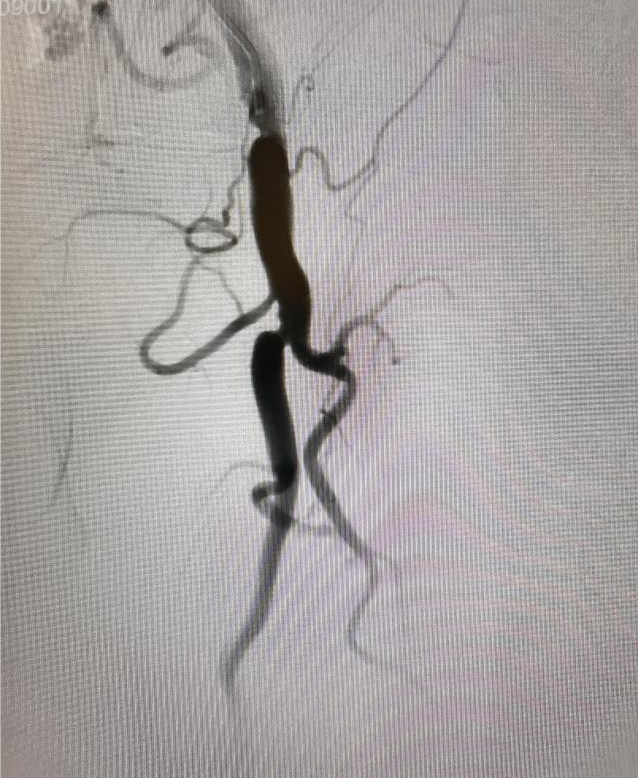

(图2:下肢造影提示左侧股浅动脉闭塞)

(图3:导丝逆向通过病变,到达正向单弯导管中)

面对这一技术挑战,刘超医生提出创新性解决方案:“正向不通,就尝试逆向突破。”在充分术前准备和严密风险评估基础上,手术团队果断采用逆行介入技术:于患者膝关节上方约2厘米处对股浅动脉远端进行精准穿刺,同步从近端与远端双向推进导丝。术中巧妙运用超滑导丝配合强支撑导管,实施“双向穿针引线”策略,最终成功实现导丝在闭塞段内的精准“会师”,逐步打通顽固性阻塞,恢复下肢动脉血流。术后患者下肢灌注明显改善,双下肢无力症状显著缓解,恢复情况良好,目前已可逐步开展康复训练。